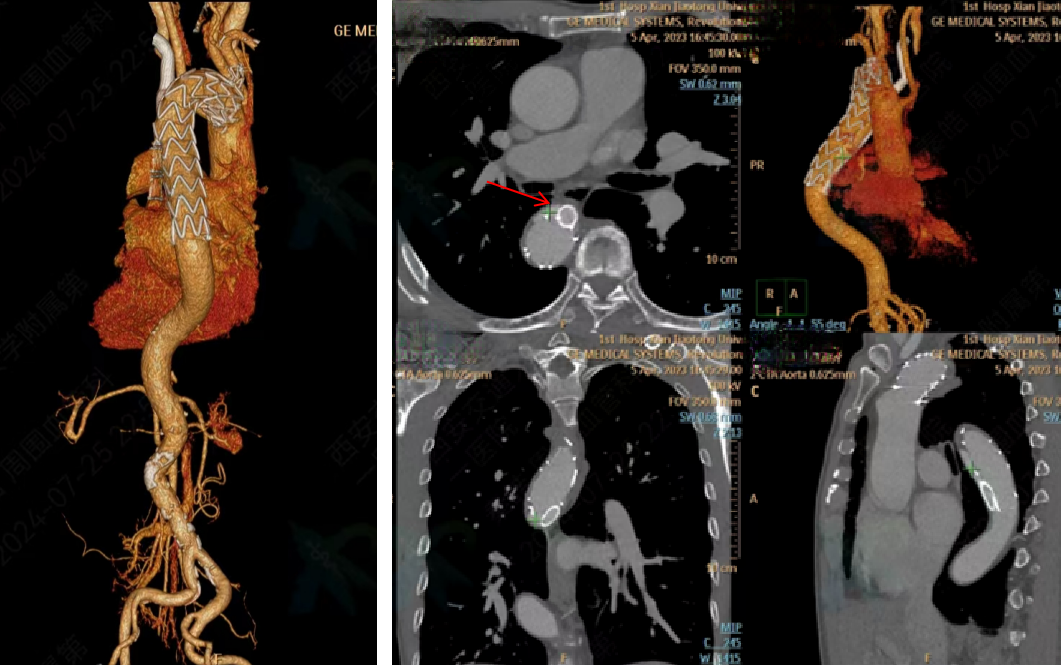

★Case 4 主动脉夹层+ARSA

治疗难点:弓上分支变异,迷走右锁骨下动脉+Kommerell憩室,夹层破口位于ARSA根部,累及LSA

手术策略:单分支支架,分支重建迷走右锁骨下动脉+续接覆膜支架

结果:假腔完全隔绝,弓上分支通畅